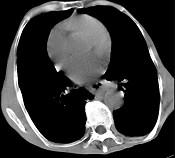

问题 女,71岁,进食时有梗阻感,进行性加重半年,影像检查如图,最可能的诊断是 ( )

选项 A.贲门失弛缓症 B.食管癌并纵隔淋巴结转移 C.食管良性狭窄 D.反流性食管炎 E.食管静脉曲张

答案 B